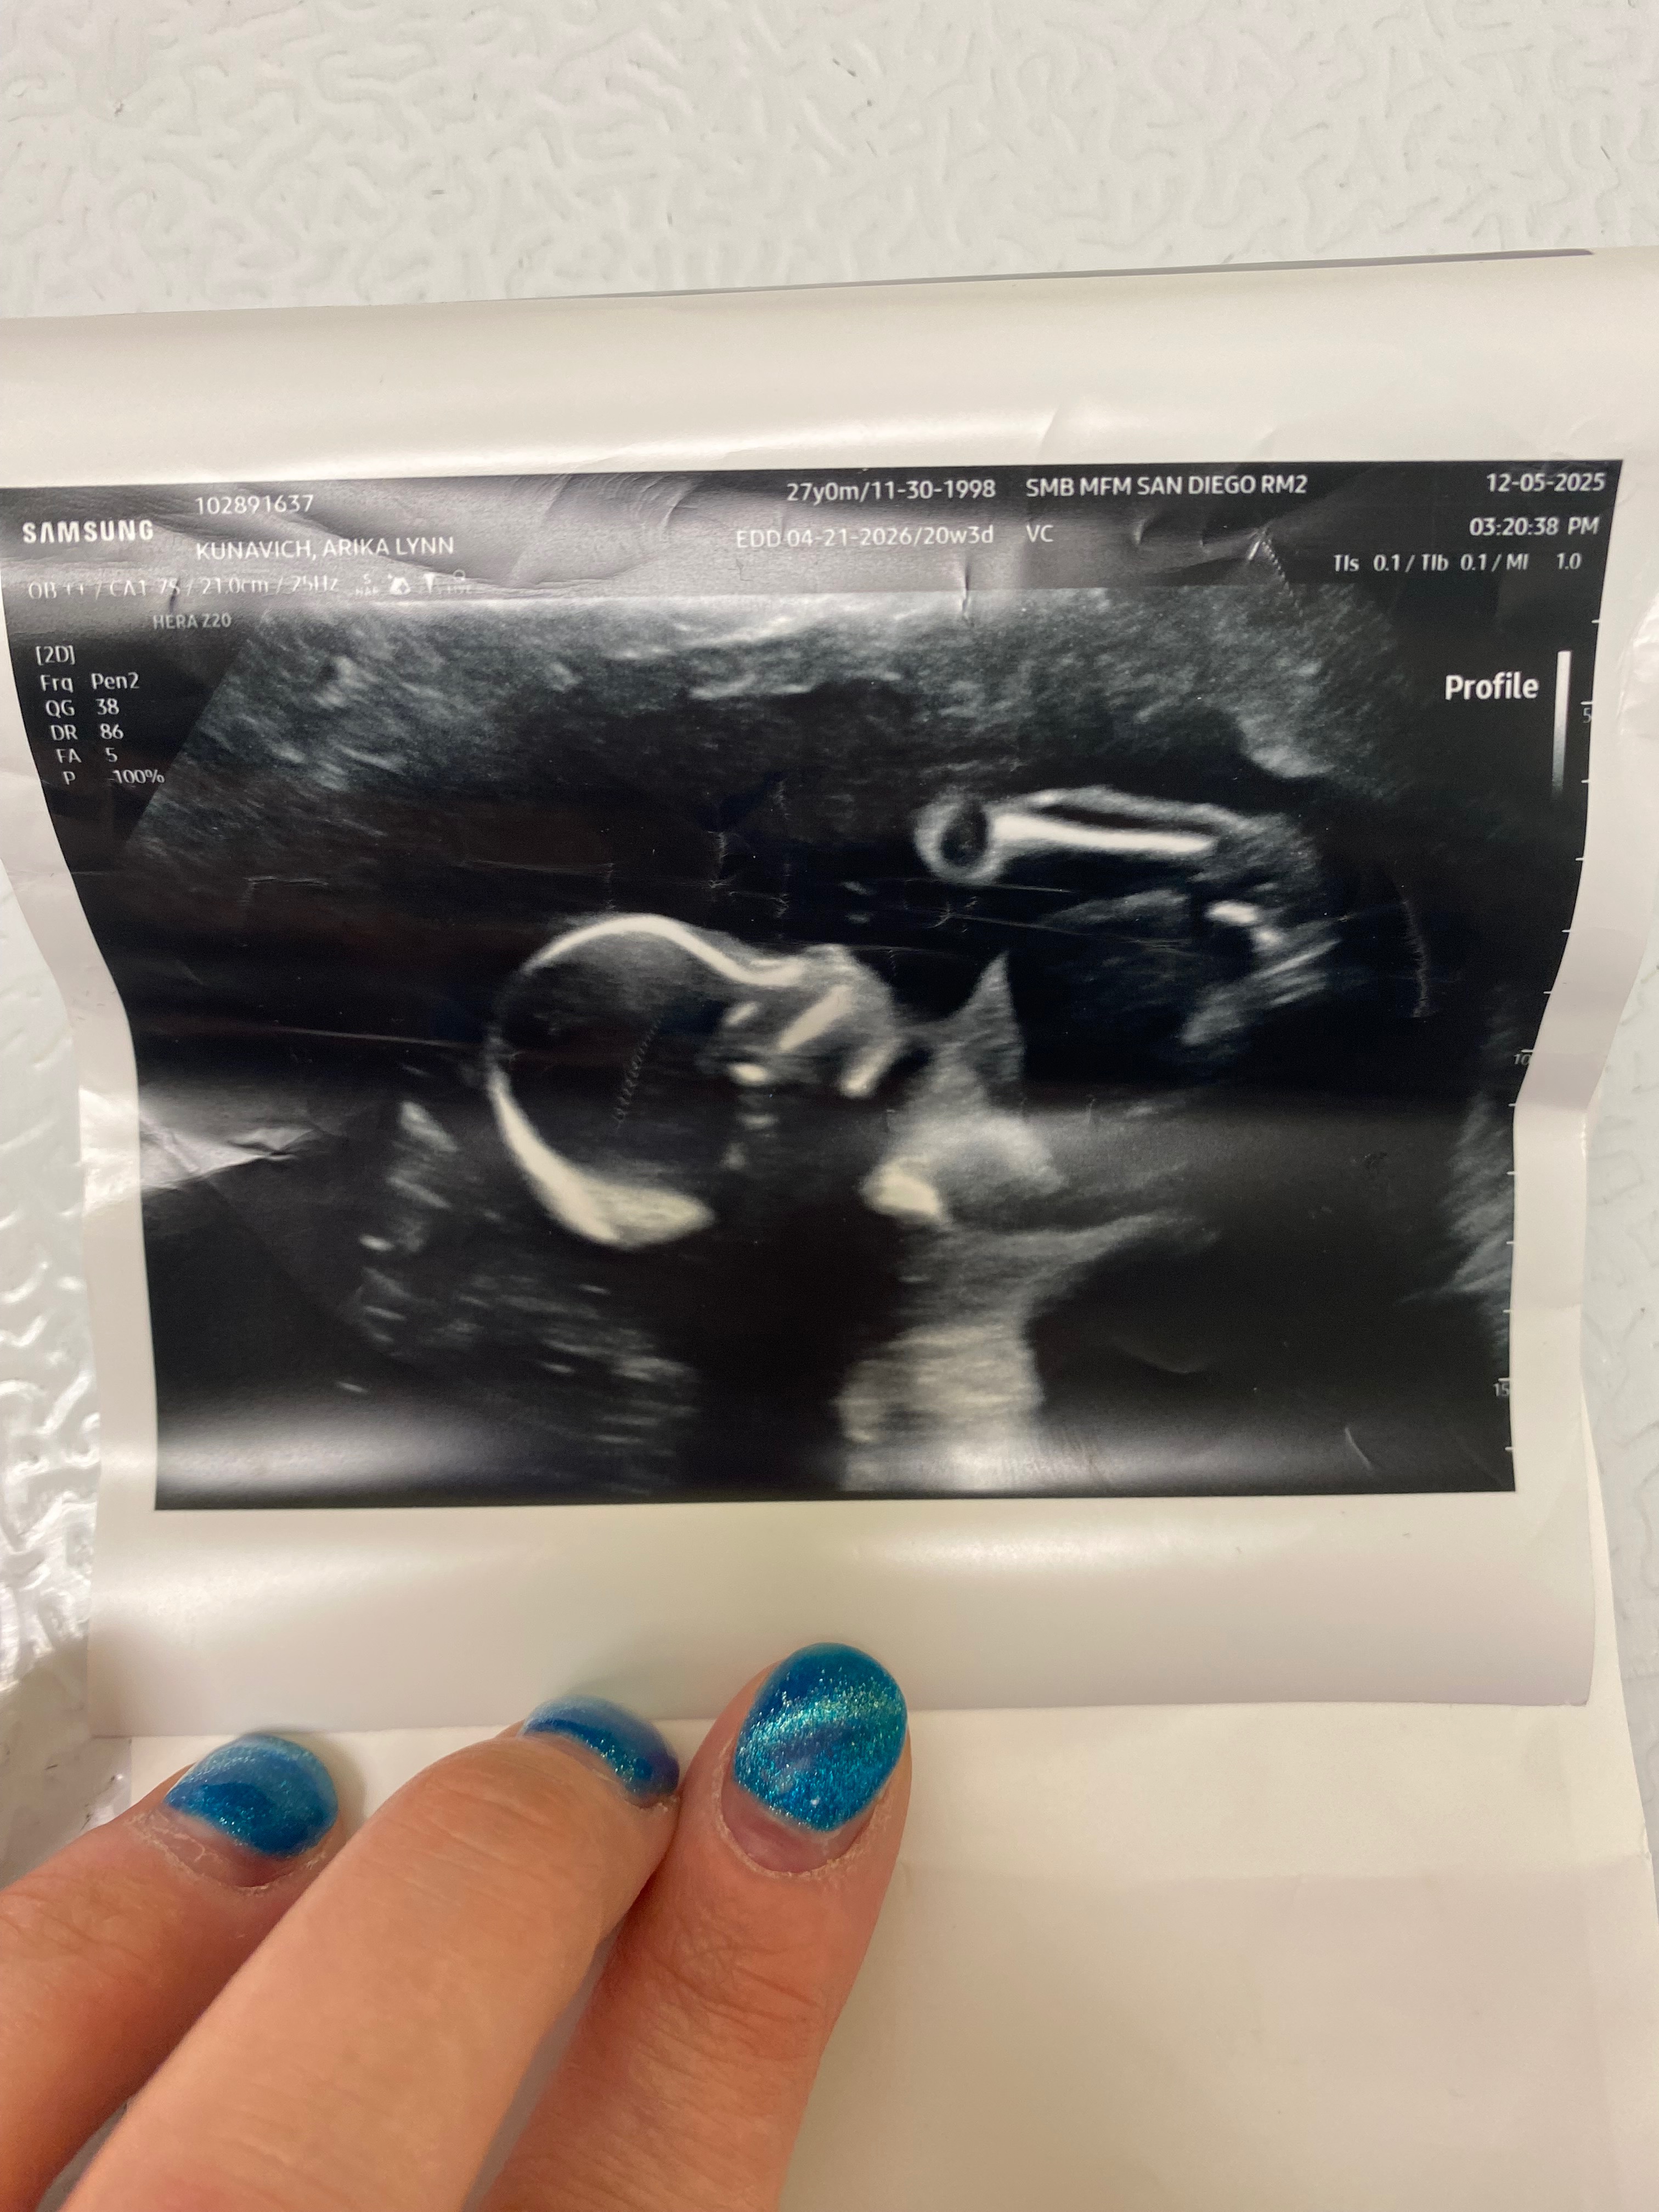

on 12/5/2025 our lives were changed forever. what was supposed to be a happy time, our 20 week anatomy scan turned into a living nightmare.

Kyrie Kay was diagnosed with spina bifida myelomeningocele with chiari malformation. She had other disabilities/abnormalities due to her neural tube defect which we are keeping private.